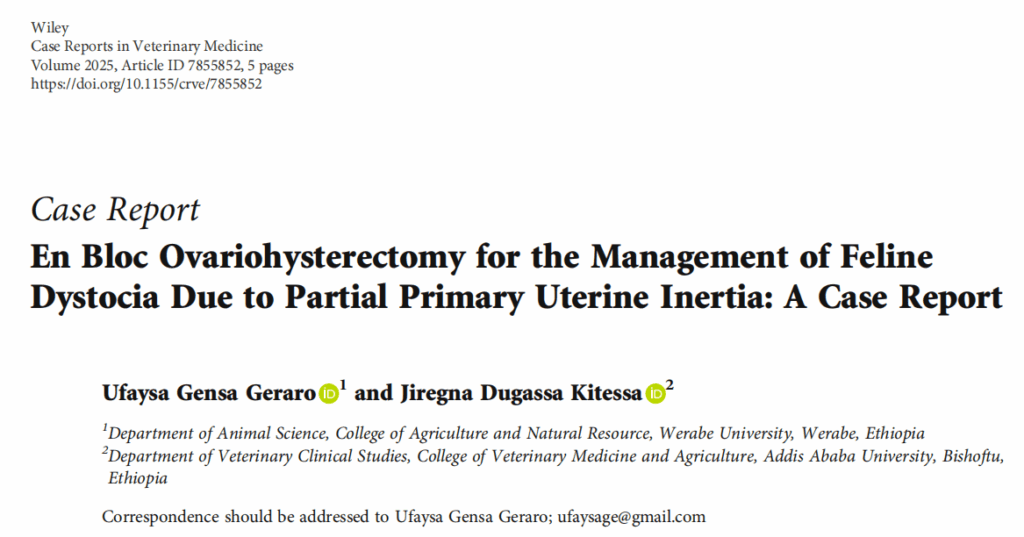

在手术台上进行仰卧和纱布绑扎后,按照标准卵巢子宫切除术在脐部和耻骨之间的中三分之一处进行后腹中线切口。钝性分离皮下脂肪和结缔组织,露出白线,白线被切开以进入腹腔。暴露妊娠子宫(下图),腹部内脏用无菌纱布填充。

↑ 外露的子宫内含胎儿。